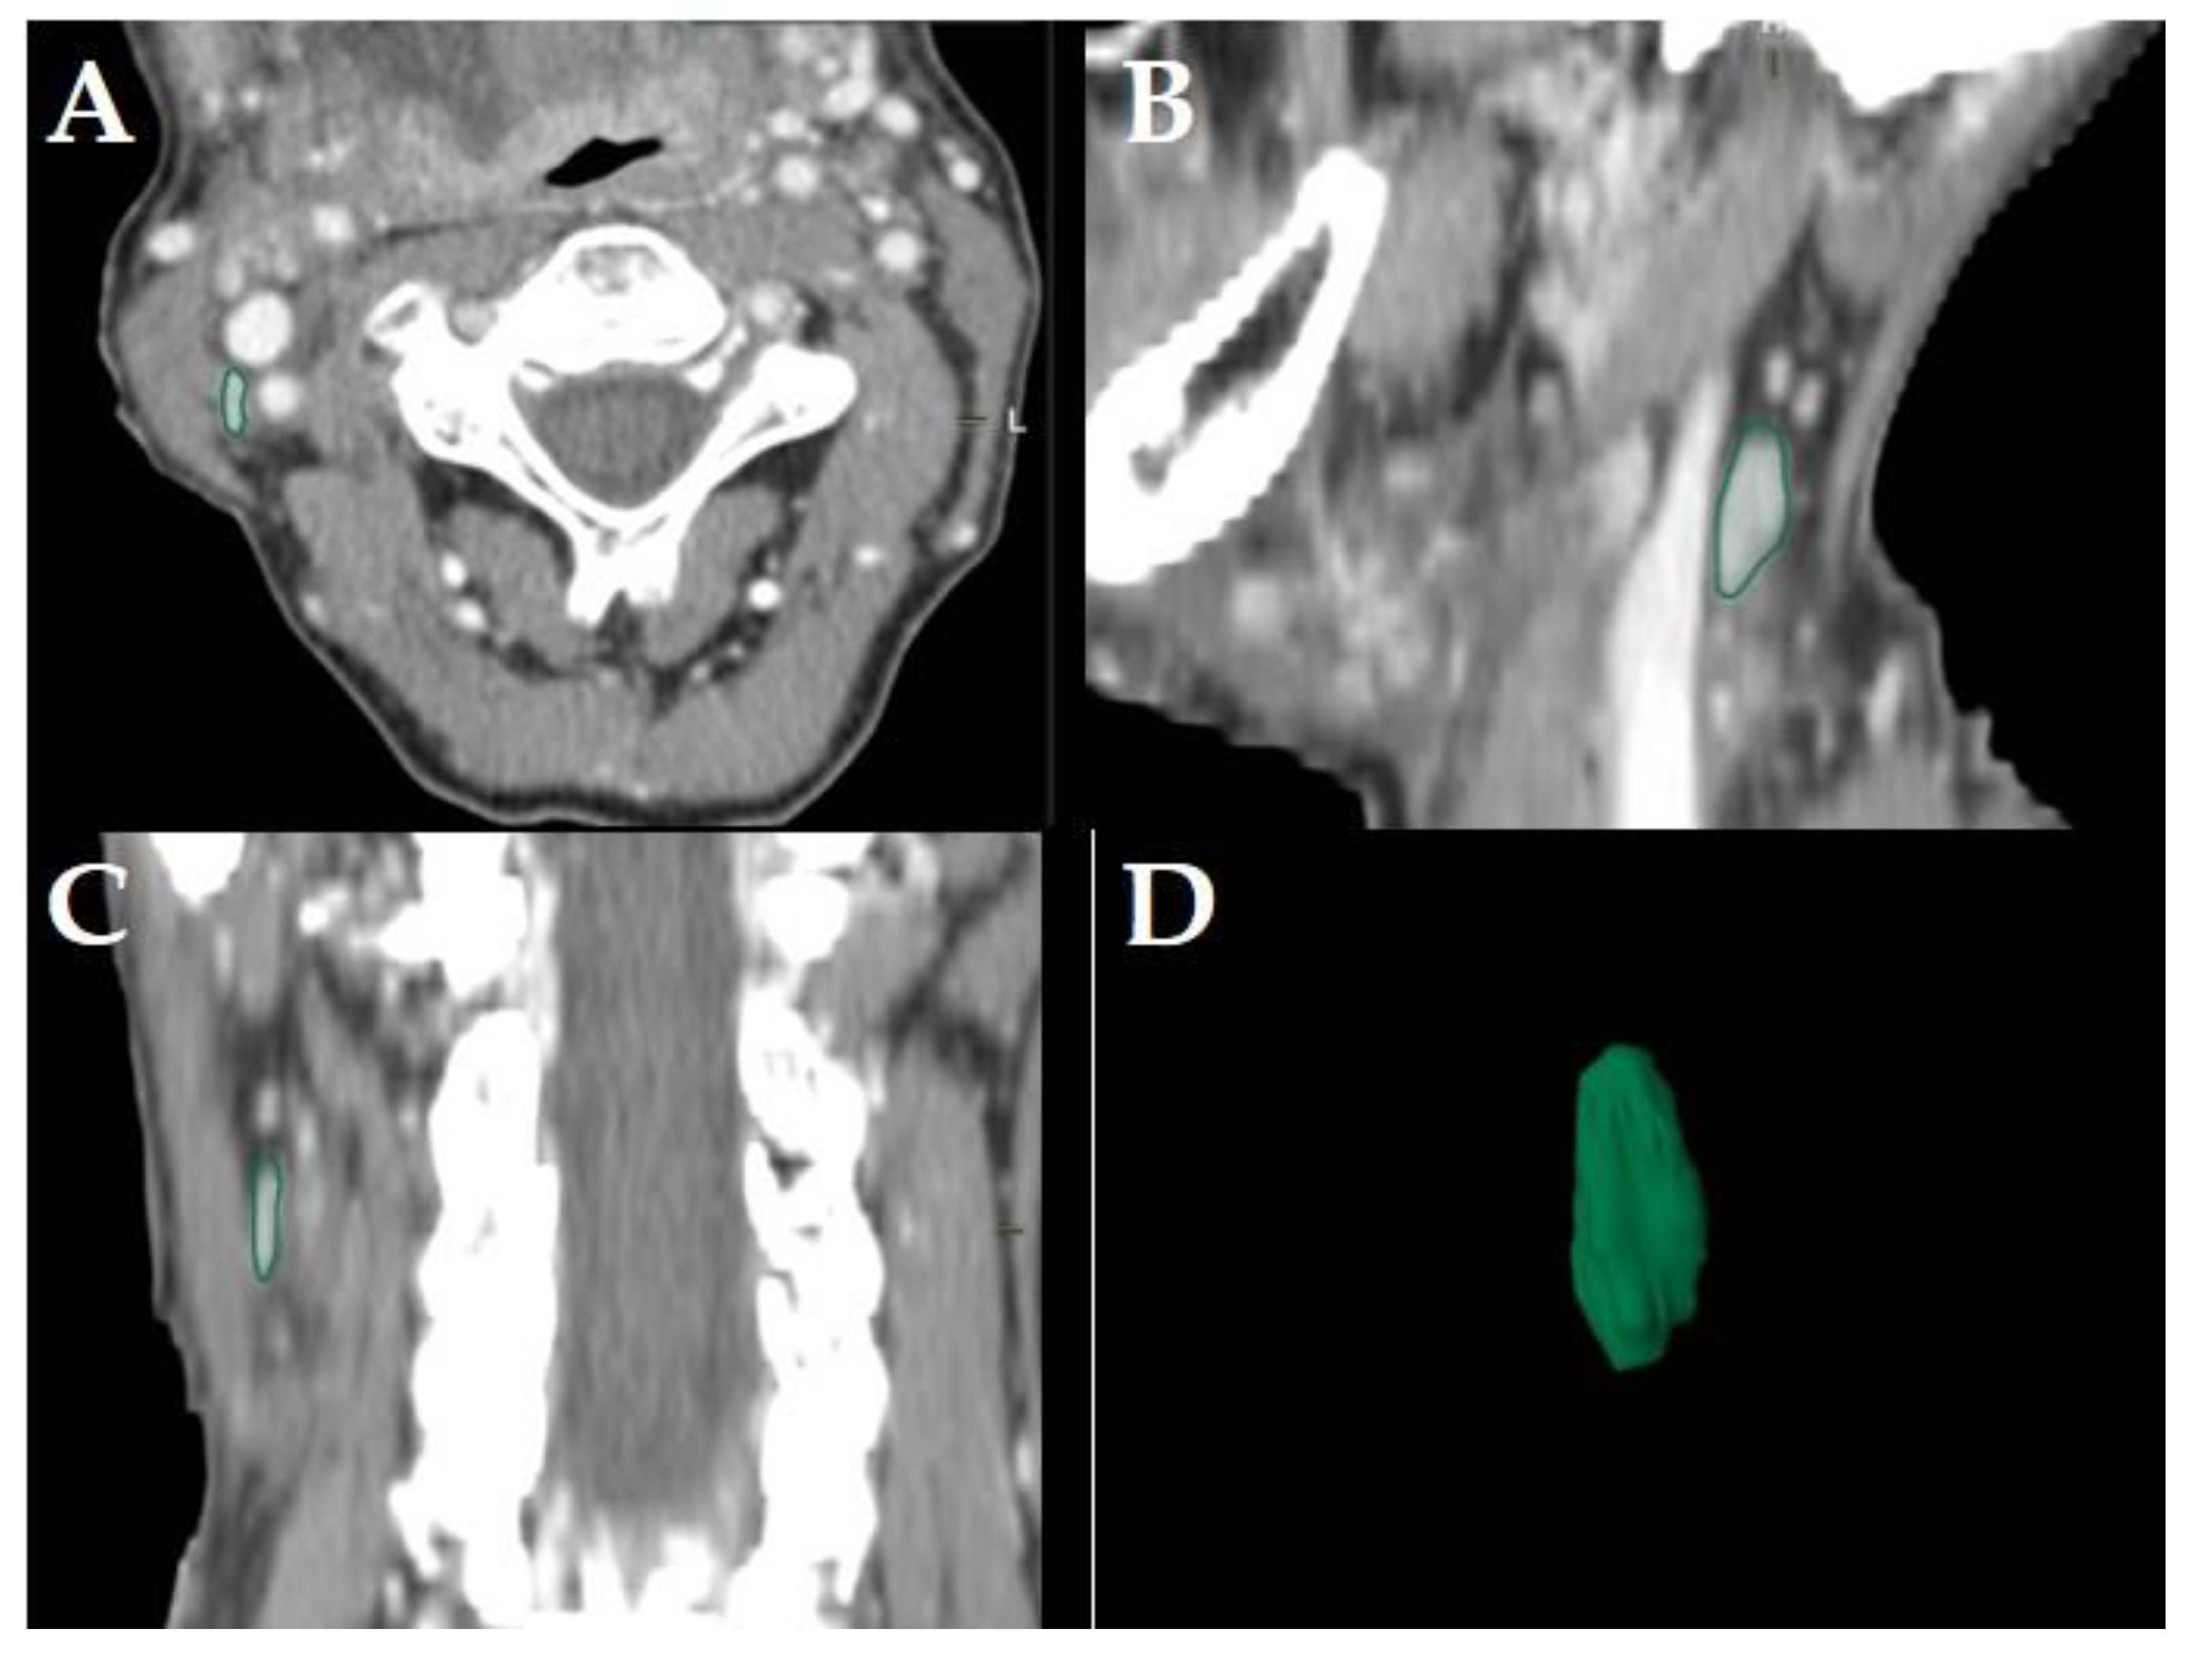

Figure 2. Example of a LN classified as “pathologic” in a staging-CT of a 55-year-old, male HNSCC patient with a tumor of the oral cavity staged cT4a cN2b cM0. Original segmentation in the axial plane (A); sagittal (B) and coronal (C) reformatted views and three-dimensional rendering (D) of the LN are provided by the software. Dashed arrows show central necrosis; no soft tissue infiltration and irregular LN capsule was observed.

LNs were classified “pathologic” in staging- and planning CTs, if axial diameters were >10 mm, LN margins were poorly defined, capsular contrast agent enhancement and/or central necrosis was observed [5]. LNs were classified “pathologic” if in restaging-CTs (i.e., after primary concurrent RCT), the maximum short axis LN diameters was >10 mm, focal LN abnormalities (lucencies, contrast-enhancement or eccentric LN bulging) were observed, and/or if an increase of the maximum short axis LN diameter of >2 mm in restaging-CTs was observed [6] (Figure 2).

Consequently, the classification of the segmented LNs in “pathologic” (Figure 2), “pathologic with ECS” (Figure 3) and “non-pathologic” (Figure 4) by the two experienced head-and-neck-radiologists based on established criteria [5,6,7] was defined as reference.